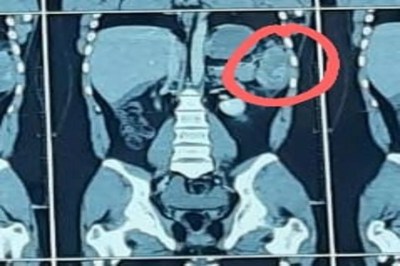

अस्पताल के जनरल सर्जरी विभाग के डॉ. तपन शाह ने बताया कि एल.जी. अस्पताल में हाल ही में तिल्ली संबंधी दो केस सामने आए। एक 45 वर्षीय महिला को सड़क हादसे में पेट और पसलियों की चोट लगी। शुरुआती रिपोर्ट सामान्य रही, लेकिन दो घंटे में रक्तचाप गिरने पर तत्काल ऑपरेशन कर तिल्ली निकालनी पड़ी। वहीं 22 वर्षीय युवक रात में दुर्घटना के बाद आया, उसे पेट, सिर और चेहरे पर चोट थी। सीटी स्कैन व सोनोग्राफी से तिल्ली की चोट की पुष्टि हुई। चार दिन निगरानी और उपचार के बाद उसे स्थिर स्थिति में छुट्टी दी गई।पेट के बाएं हिस्से में तिल्ली का आकार भले ही मुट्ठी भर है लेकिन यह हमारे लिए काफी महत्वपूर्ण अंग है। इस अंग में 400 से 700 मिली रक्त संग्रहित रहता है। यह स्पंज जैसा अंग है और चोट लगने पर जल्दी फट जाता है। यदि गोल्डन ऑवर’ में उपचार न मिले तो अत्यधिक रक्तस्राव से जीवन संकट में पड़ सकता है।